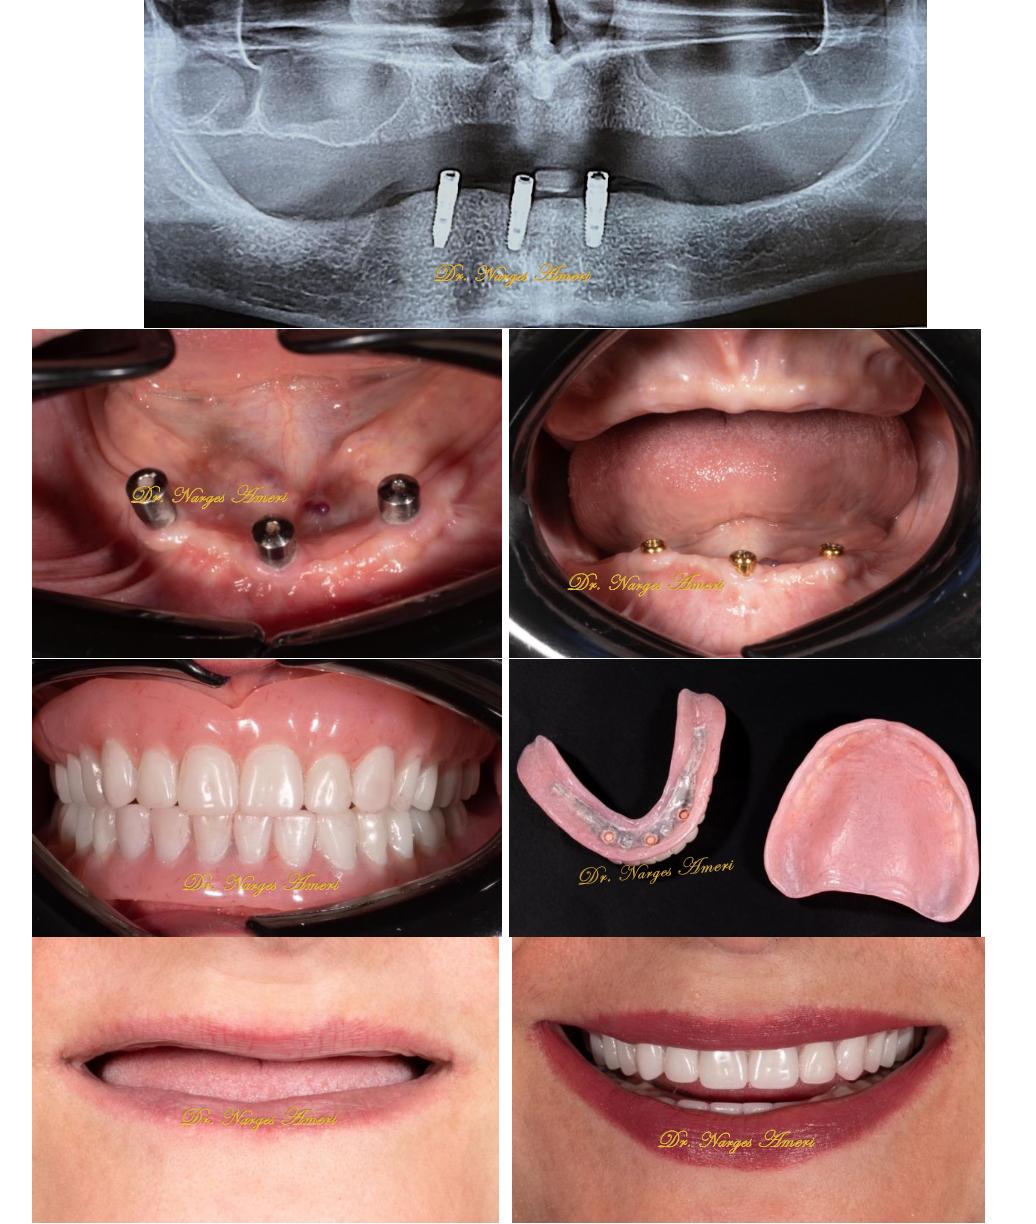

Implant-Supported Overdenture

Implant-supported overdenture with locator attachments for improved retention